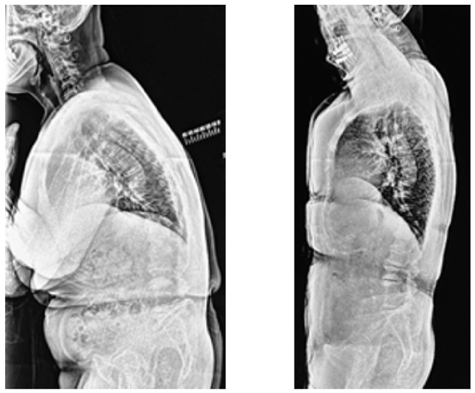

Effects of Pilates Exercise on Age-Related Kyphosis

Junzo Fujitani, Kazuta Yamashita, Fumitake Tezuka, Kosuke Sugiura and Koichi Sairyo. 14(2): 15-21.